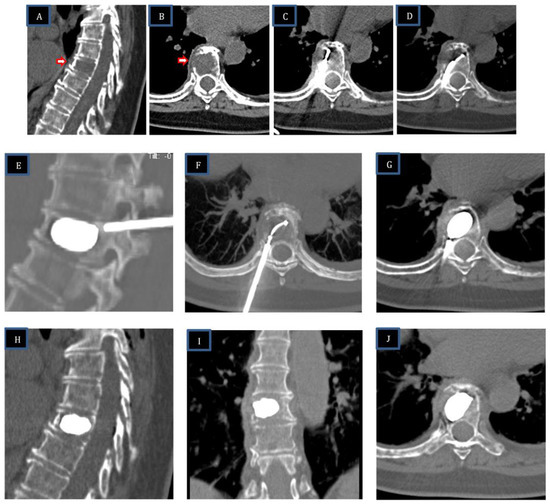

Figure 4. Painful pathological fractures of T8–T9 from lung carcinoma (patient #5-Table 1). (AC): Axial and sagittal CT images of aggressive destructive osteoblastic metastasis of the T8–T9 vertebral bodies (blue arrows in (A)) with pathological fracture and destruction of the posterior wall of the T8 vertebra (red arrow in (B)). (D): Placement of the STAR™ radiofrequency probe (white arrow) in the central portion of the T8 vertebra lesion. (E,G): Vertebroplasty on the T9 vertebra, given the absence of posterior wall rupture. (F): The Arcadia™ low-compliance, high-pressure balloon was coaxially inserted into the introducer cannula and deployed into the lesion (red arrow). Note the inflation of the low-compliance Arcadia balloon after RFA and the predictable cement distribution. (HJ): Post-vertebroplasty CT (H) and MRI (I,J) sagittal images post procedural control T8 and T9 without complications.